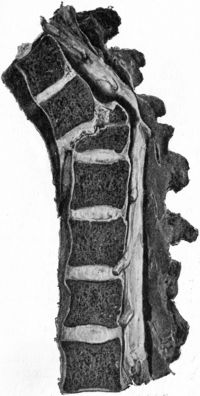

| 211. | Osseous Ankylosis of Bodies (a) of Dorsal Vertebræ, (b) of Lumbar Vertebræ following Pott's Disease | 434 |